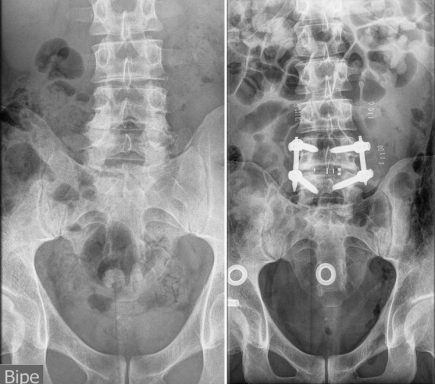

Me detectaron una gran herniación en L4-L5, y bastantes discos desgastados.

Cuando a pesar de la medicación, el deporte, y mi vida saludable, llegó un punto en el que ya no sentía alivio, decidí volver al traumatólogo para comprobar que la hernia no estaba pinzando demasiado la raíz, pero la sorpresa fue que en la RMN, se observaba la existencia bastante evidente de Romanus. Mucho más del que pueda verse en cualquier degeneración vertebral por el paso del tiempo.

Mi afectación consiste en dolor en columna cervical y lumbosacra, (Las sacroiliacas muy comprometidas) cadera, rodillas, tendones, muñecas, fatiga muscular y respiratoria, uveítis esporádicas, e inflamación intestinal y en consecuencia, sangrados.

Las vértebras L4-L5, totalmente colapsadas, y apófisis transversas impactando en la cresta iliaca, dieron el resultado final de una cojera permanente, por lo que me realizan una artrodesis lumbar con OLIF.